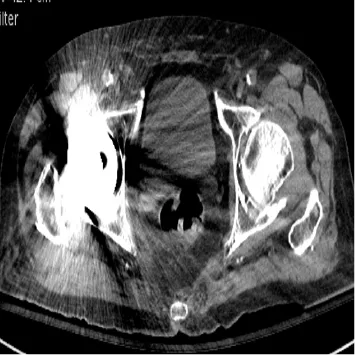

L’avancée la plus récente mais également la plus significative est l’introduction d’un nouveau type de reconstruction des images, la reconstruction itérative [7] : depuis la découverte de la technique du scanner par Sir Hounsfield, les images étaient reconstruites par rétroprojection filtrée. La reconstruction itérative est plus complexe sur le plan mathématique et était impossible à mettre en œuvre avant les progrès récents de l’informatique. La méthode consiste à reconstruire l’image par hypothèses successives appelées itérations. Il existe plusieurs techniques différentes selon les constructeurs. Toutes ces méthodes permettent de diminuer très significativement la dose délivrée au patient, puisqu’elles améliorent le rapport signal/bruit des images même celles initialement bruitées. L’ensemble des machines actuellement disponibles sur le marché proposent cette méthode et elle est donc utilisée de façon routinière sur les examens abdominaux. Ces méthodes permettent également de limiter les artéfacts métalliques (dit de renforcement de faisceaux) que l’on observait avec la reconstruction filtrée (Fig. 2) [8].

Figure 2. Comparaison de la même image reconstruite par rétroprojection filtrée (A) et par reconstruction itérative (B).

Les artéfacts liés à la prothèse de hanche sont diminués sur le mode itératif